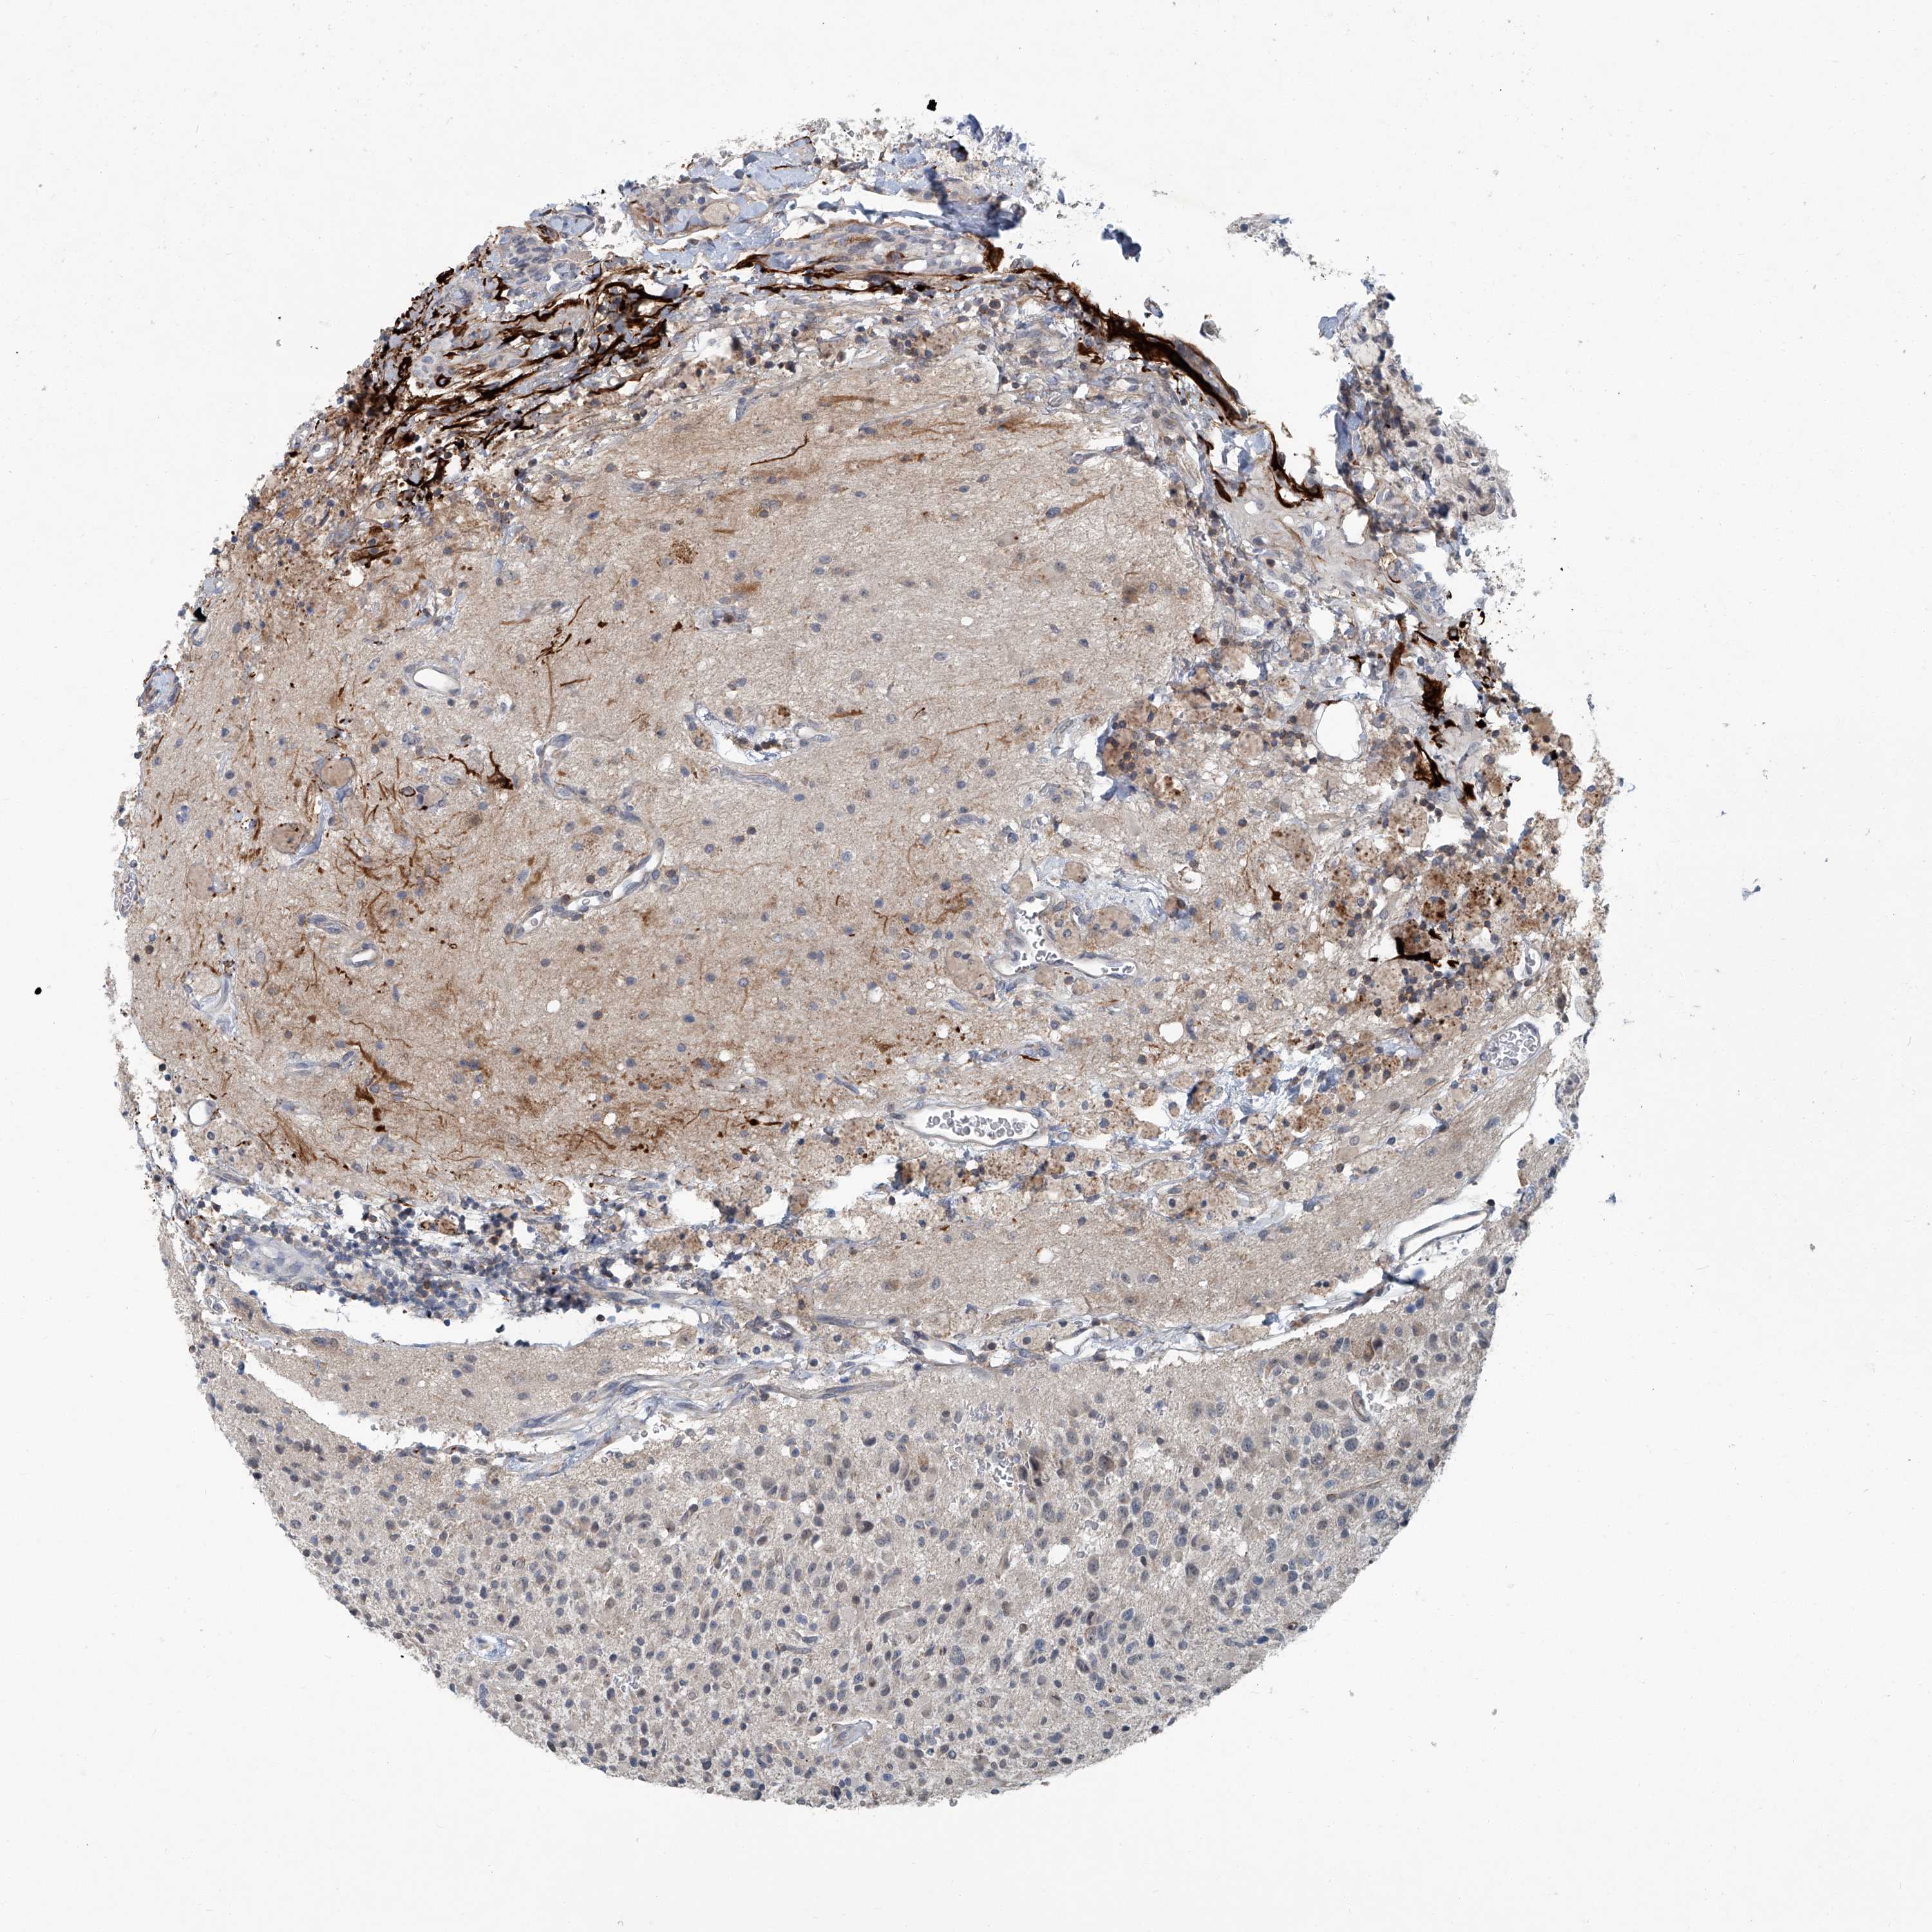

GLIOMA - Protein expressioni

A mouse-over function shows sample information and annotation data. Click on an image to view it in a full screen mode. Samples can be filtered based on level of antibody staining by selecting one or several of the following categories: high, medium, low and not detected. The assay and annotation is described here.

Note that samples used for immunohistochemistry by the Human Protein Atlas do not correspond to samples in the TCGA dataset.

Antibody stainingi

Antibody staining in the annotated cell types in the current human tissue is reported as not detected, low, medium, or high, based on conventional immunohistochemistry profiling in selected tissues. This score is based on the combination of the staining intensity and fraction of stained cells.

Each image is clickable and will lead to virtual microscopy that enables deeper exploration of all samples and also displays staining intensity scores, fraction scores and subcellular localization as well as patient and tissue information for each sample.

Antibody HPA030270

Antibody HPA030271

Antibody HPA030272

Staining

High

Medium

Low

Not detected

Intensity

Strong

Moderate

Weak

Negative

Quantity

>75%

75%-25%

<25%

None

Location

Nuclear

Cytoplasmic/membranous

Cytoplasmic/membranous,nuclear

Glioma, malignant, High grade

Glioma, malignant, Low grade

Glioblastoma, NOS